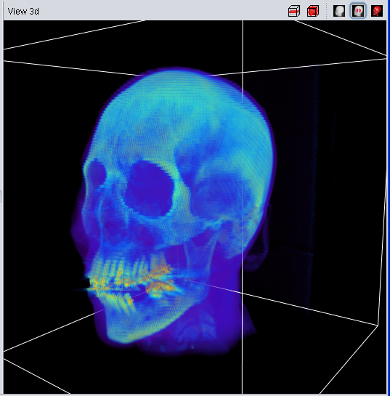

| Volume Data using 2D Texture | Volume Data using 3D Texture |

The 3D-Texture Visualization is very similiar to the 2D-Texture Visualization, but usually with a usually improved rendering quality. Since not all graphic cards support 3D-textures (yet), both visualization features have been implemented. If the "View 3d" shows only a "white box" instead of the loaded data, your graphic card does not support 3D-Textures.

Experts Tip: The ROI-Selection (in the "Misc" panel in the tool pane) has an immidiate influence on the 2d/3d texture visualization.